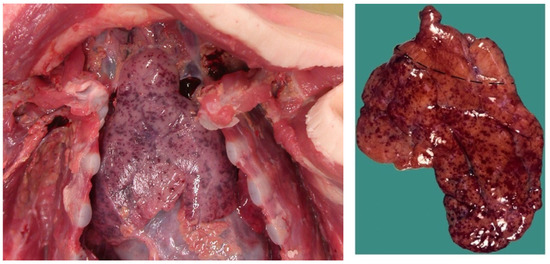

It is proposed that respiratory arrest by DCC is responsible for some SIDS and SUDC cases as well as some SCD in adults. Like the novel obstruction of OSA outlined above, where diaphragm spasm mechanically resists RAM contractions (causing transient apneas-hypopneas), sustained apneas would occur in DCC. If not overcome by autoresuscitation or rescue breaths, asphyxia and death will ensue. Unfortunately, like ventricular fibrillation, pathological pump contractions are temporary and do not persist postmortem, making it impossible to confirm at autopsy. However, Kariks (1989) [143] found indirect evidence in the diaphragms of SIDS victims. Although controls were not provided, contraction band necrosis was present in 82% of diaphragms (D-CBN) along with focal-to-diffuse myofiber ruptures (sarcomere disruptions) and fibrous scars. Acute inflammatory cell infiltrates were not seen (suggesting a hyperacute process). Tissue staining revealed that some sort of diaphragmatic hypercontraction injury (causing irreversible sarcomeric spasm) had occurred terminally and acutely under prolonged anoxia, leading to contracted segments of thick and thin muscle filaments. Fibrous scars in various stages of healing suggested prior non-fatal injuries had occurred by repeated HE in the preceding days to weeks. Silver & Smith (1992) [144] confirmed these myopathic findings, stating D-CBN was common in 125 neonates and infants that had died suddenly, primarily by asphyxia. This included birth asphyxia, drownings, suffocation, severe burns with carbon monoxide poisoning and SIDS. Other modes of death included meningitis, head injuries and acute dehydration from severe gastroenteritis [86]. They remarked, “The morphologic age and, if present, stage of healing in each case suggested that the diaphragmatic lesion commenced at or shortly before death or at the time of the cardiac arrest that led to death”. Despite such compelling results, and a few other reports, research in this promising area stalled. Regardless, the evidence makes it imperative to start including diaphragm histology in all autopsies involving sudden unexpected deaths.

Similar histopathologic changes were reported in children with incapacitating leg cramps associated with viral influenza, predominantly serotype B. Conducted by retrospective analyses of hospital cases of influenza-associated myositis (IAM) as well as case reports and reviews articles, Agyeman et al. (2004) [147] found that calf muscles alone or together with other limb muscle groups (undisclosed types) were involved in 69% and 31% of a combined 316 cases, respectively. There was a gender ratio of 2:1, male–female, in these school-aged children of median 8.5 years of age (range 2.5–14). Serum creatine phosphokinase (CPK, or creatine kinase, CK) levels were massively elevated along with lactic dehydrogenase and aspartate transaminase. Skeletal muscle troponin-I (STnI) is even more sensitive and specific [148]. Ten children (3%) developed severe rhabdomyolysis, eight had acute renal failure, two required MV, and another one died. The authors referenced other calf muscle biopsy reports in pediatric IAM, demonstrating patchy necrosis with scant inflammatory infiltration in 11 of 12 in one series and 28 of 35 with muscle degeneration, necrosis, and scant infiltrates in another. Because of the lack of infiltration, the authors used the term myopathy in lieu of myositis. All such findings are important because the diaphragm too could be vulnerable to “direct muscle invasion by virus particles or immune-mediated muscle damage.” This could have been responsible for the two cases requiring MV and the one who died. Cell injury along with inflammatory mediators might have contributed to progressive diaphragm fatigue, excitation, and ultimate respiratory failure. Indeed, Eisenhut (2011) [90] reported marked diaphragmatic abnormalities in a 5-month-old girl admitted with RSV bronchiolitis and poor feeding who succumbed in hospital to a sudden, unexpected death. Although grossly normal, diaphragm histology revealed myofiber destruction, focal segmental myocyte necrosis, myocyte regeneration, and focal infiltrates of macrophages and small lymphocytes. Interestingly, similar findings were reported in COVID-19 deaths in adults [47,149]. Such changes provide even more support to evaluate diaphragm histology in sudden death cases involving viral (or bacterial) infection. Moving forward, serum CK, CK-MM (skeletal muscle isoenzyme) or sTnI levels and venous blood gases could screen for and risk-stratify those at risk for respiratory decompensation by critical diaphragm fatigue and excitation.